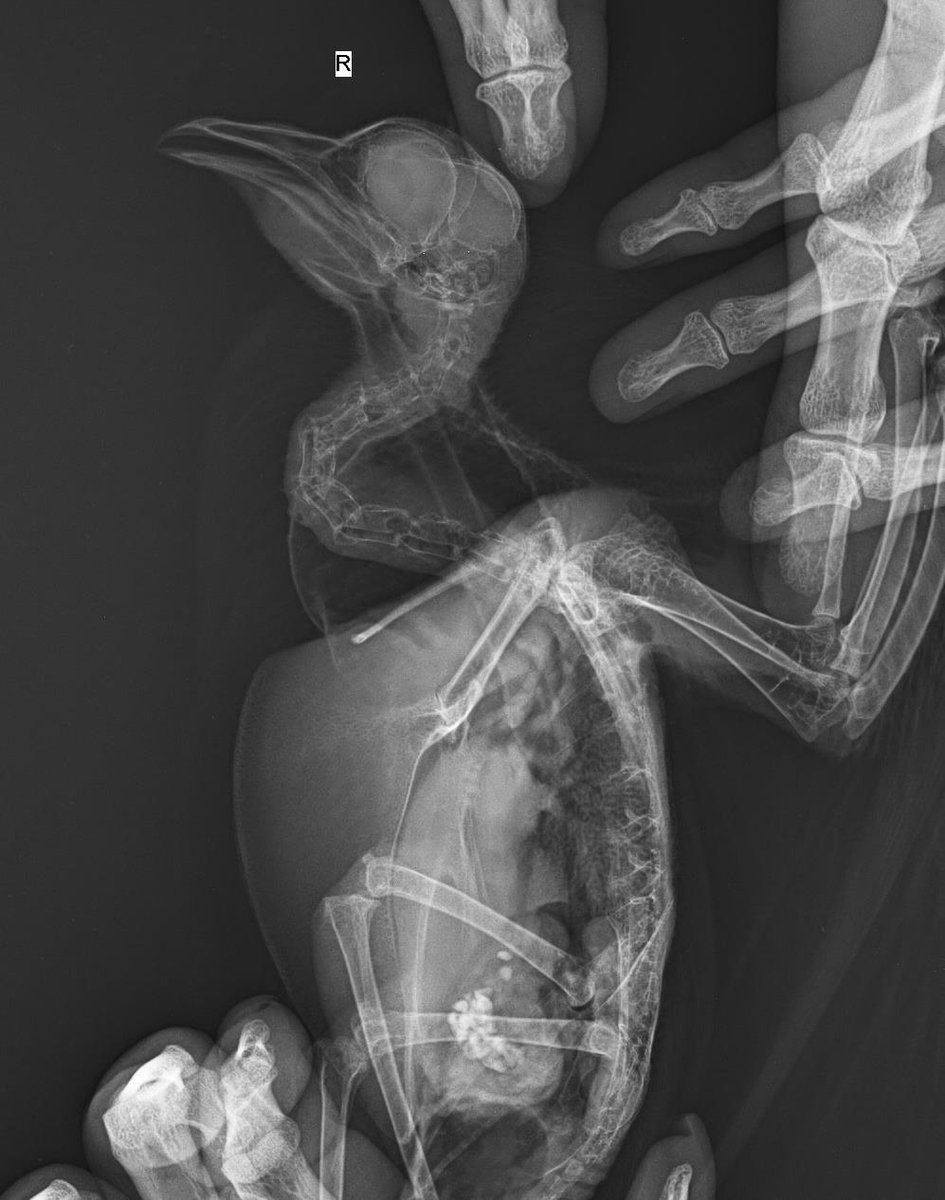

Appleness Опубликовано 28 января, 2022 Автор #46 Опубликовано 28 января, 2022 (изменено) @маленький принц сегодня в 13:30 идем ко врачу, он поставит диагноз и назначит лечение. 8:00 покормила кашей из шприца, перья немного почистила, помет все тот-же ярко-темно-зеленый, без крови рассмотрела сегодня горло, там совсем маленькая дырочка для глотания, ему тяжело глотать большие объемы @маленький принц я понимаю, что вы хотите помочь, но тут несколько врачей, все пишут разное, я не понимаю кого мне слушать. На приеме спрошу сегодня про орнидазол и метрогил. @OFA @Zosia можете рентген посмотреть, я так и не поняла, можно по нему как-то диагноз ставить или хотя бы что-то исключить? У меня получилось рассмотреть рот У него есть язык, но он скрыт под чем-то непонятным. Это или опухоль, или киста, или что-то еще. у этого чего-то есть темное пятно, но в целом оно светлое, размеров с шарик около 5мм. Именно это образование мешает глотать, и не дает проникнуть в горло ватной палочкой. Во рту слизи нет. попробую его покормить инсулиновым шприцом, справа(со стороны голубя ) рта есть доступ к горлу, слева этот шарик Изменено 28 января, 2022 пользователем Appleness

маленький принц Опубликовано 28 января, 2022 #48 Опубликовано 28 января, 2022 1 час назад, Appleness сказал: У него есть язык, но он скрыт под чем-то непонятным. Это или опухоль, или киста, или что-то еще. у этого чего-то есть темное пятно, но в целом оно светлое, размеров с шарик около 5мм. Именно это образование мешает глотать, и не дает проникнуть в горло ватной палочкой. это и есть нарост можете сделать фото и СРОЧНО начать лечение читайте про трихоминоз https://www.mybirds.ru/forums/topic/65174-trihomonoz/ 1 час назад, Appleness сказал: @Zosia можете рентген посмотреть, я так и не поняла, можно по нему как-то диагноз ставить или хотя бы что-то исключить? рентген у Вас получился просто идеальный если Зося на нём что-то заметила бы она бы написала 41 минуту назад, Appleness сказал: 8:45 получилось! инсулиновый шприц вставила в горло (в голубе был только кончик шприца, толстая часть снаружи). раньше я просто наливала в рот жидкую кашу, много разбрызгивалось. сейчас получается всю кашу ввести в голубя. и поэтому кашу я сделала уже более густую. через три часа после кормёжки нужно фото помёта кончик шприца перед кормлением смазать снаружи Метрогил-дента